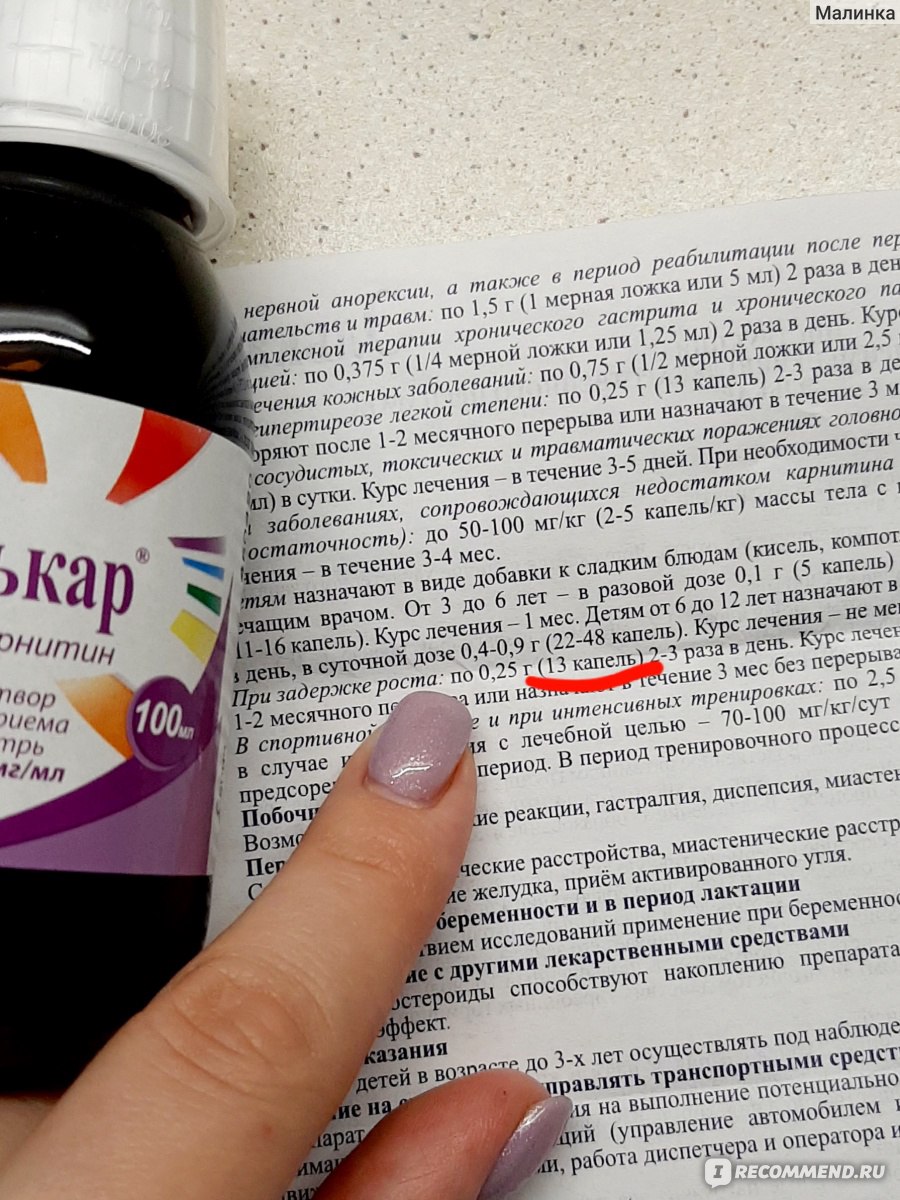

Приобретая Элькар в каплях, обратите внимание на инструкцию по приему, особенно, когда это касается детей. Элькар в каплях выпускается в виде 20% раствора и Элькар 30%

Инструкция по приему разная.

Элькар в каплях 20% чаще назначается новорожденным и детям до трехлетнего возраста, поскольку препарат этой концентрации легче дозировать. Детям с 3 лет и старше назначают Элькар 30%. Не перепутайте, Элькар 30% по инструкции назначается в гораздо меньшей дозировке, чем Элькар 20%.

Элькар 20% по инструкции для детей в возрасте до 1 года назначается по 10 капель 3 раза в день. Элькар 20% по инструкции для детей от 1 года до 6 лет назначается по 14 капель 3 раза в день. Возможно применение препарата в виде добавки к компоту или соку. Детям в возрасте от 6 до 12 лет препарат назначают по 1/4 чайной ложки 2 раза в день.

Элькар 30% по инструкции назначают детям от 3 до 6 лет по 5 капель 2-3 раза в день. Детям от 6 до 12 лет элькар 30% согласно инструкции назначают по 11-15 капель 2-3 раза в день.

Во всех случаях Элькар в каплях согласно инструкции принимают за 30 минут до еды, предварительно разбавив жидкостью. Именно такой режим приема обеспечивает полное всасывание препарата. Курс приема препарата зависит от заболевания и состояния ребенка. Максимально выраженный эффект от приема препарата наблюдается после приема в течение 5-6 месяцев.